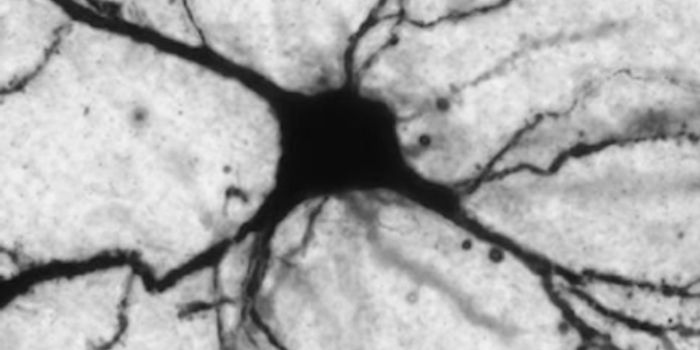

Read the latest articles about newly released neuroscience research and advances in experimental techniques. Topics include research news in neuroscience, neurology, psychology, brain science and cognitive sciences.